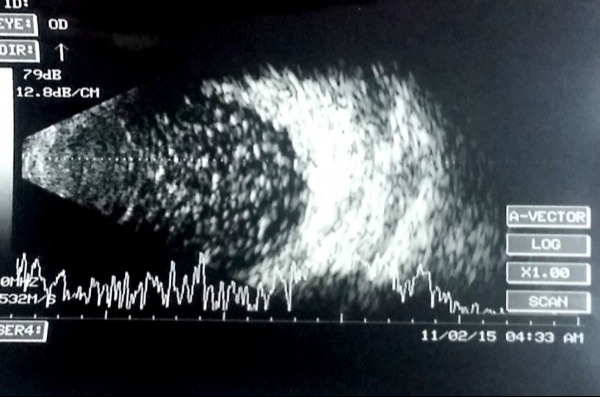

Hemorragia vítrea que impide la visualización del fondo.

Evaluación preoperatoria en casos de vitrectomía.

Control postquirúrgico de cavidad vítrea.